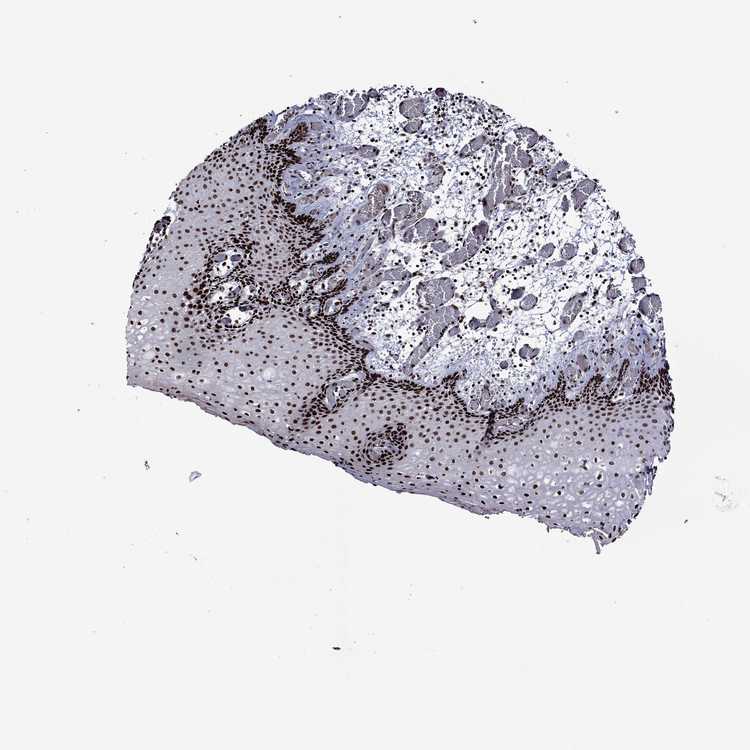

ESOPHAGUS - Antibody stainingi

Antibody staining in the annotated cell types in the current human tissue is reported as not detected, low, medium, or high, based on conventional immunohistochemistry profiling in selected tissues. This score is based on the combination of the staining intensity and fraction of stained cells.

Each image is clickable and will lead to virtual microscopy that enables deeper exploration of all samples and also displays staining intensity scores, fraction scores and subcellular localization as well as patient and tissue information for each sample.

Antibody HPA028516Antibody HPA073571

Squamous epithelial cells HighHigh